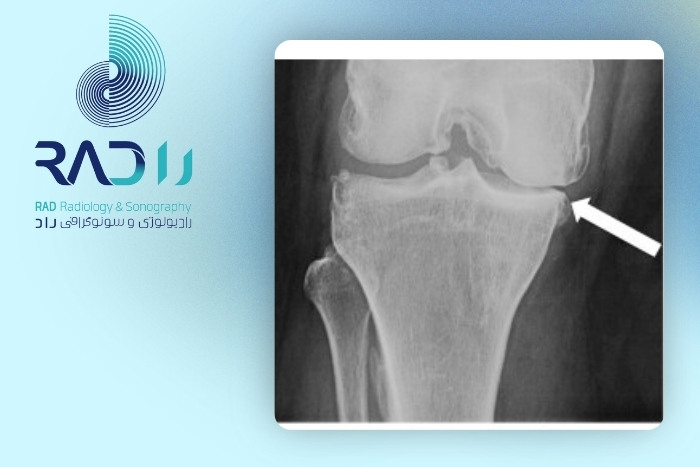

رادیوگرافی ساده یکی از رایجترین و در دسترسترین روشهای تصویربرداری مفاصل است. اما سؤال اصلی این است که آیا این روش میتواند آرتروز در مراحل اولیه را نشان دهد یا خیر. رادیولوژی درواقع استخوان را نشان میدهد نه غضروف را. چون آرتروز اولیه بیشتر از غضروف و بافت نرم شروع میشود رادیولوژی در این مرحله تغییرات آشکاری را نشان نمیدهد. تنها زمانی که فاصله مفصلی کم شود یا استخوان دچار استئوفیت گردد آرتروز در رادیولوژی قابل تشخیص میشود.

اگرچه رادیولوژی ساده در تشخیص آرتروز اولیه محدودیت دارد اما در مراحل بعدی بسیار کاربردی میشود. پزشک در مواردی مانند درد مزمن زانو یا دست، تغییر شکل مفصل، سابقه ضربه یا محدودیت شدید حرکتی رادیولوژی را تجویز میکند. رادیولوژی همچنین برای بررسی روند پیشرفت بیماری در طی زمان مناسب است. این روش به پزشک اجازه میدهد میزان تنگ شدن فضای مفصلی، وجود خارهای استخوانی و سفتی استخوان زیر غضروف را ببیند. حتی در شرایطی که آرتروز اولیه با سونوگرافی یا امآرآی تشخیص داده شده باشد انجام رادیولوژی برای تکمیل بررسی ساختاری مفصل ضروری است. اگر قصد انجام رادیولوژی در بلوار کشاورز را دارید میتوانید به مرکز تصویربرداری راد با تجهیزات پیشرفته مراجعه کنید.